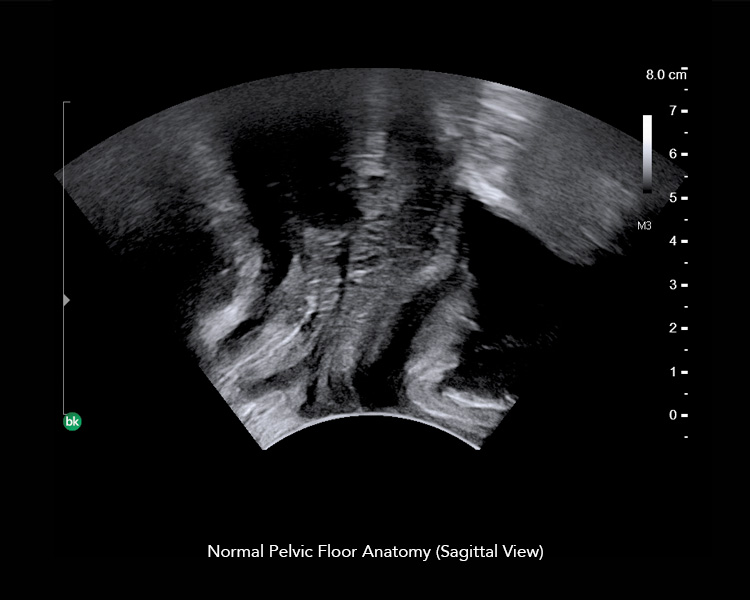

BK Medical’s ultrasound imaging with advanced 3D architecture helps you perform multicompartment pelvic floor exams, so you can visualize anatomy, plan treatment, and evaluate outcomes.

When assessing dysfunctions of the pelvic floor, experts generally promote a global approach in which the anterior, middle, and posterior pelvic compartments are examined to evaluate pelvic floor dysfunctions.

Multicompartment imaging using transperineal, endovaginal, and endoanal scanning enables you to get the information you need for the full pelvic floor picture. 3D imaging allows you review the 3D dataset after the patient’s visit.

Real-time, dynamic exams help you visualize anatomy, plan treatment, and evaluate outcomes for:

With high-definition, detailed images and an enhanced, intuitive workflow, our ultrasound imaging technology helps you visualize anatomy for the complete pelvic floor picture.